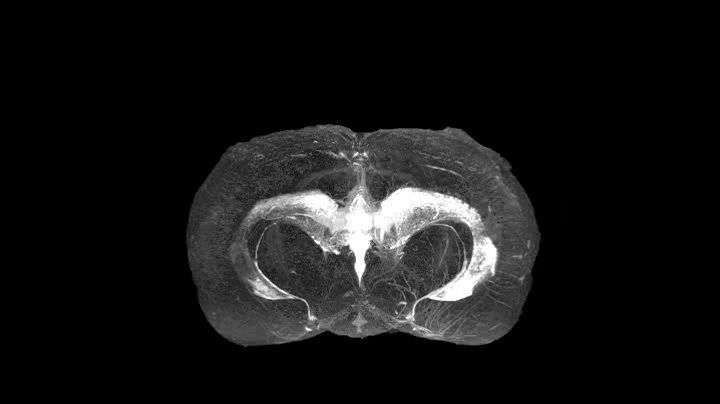

To better understand what happens under our skulls, Sarntinoranont's team injected a tracer, a compound that would show up clearly in an MRI scan, into the ventricles of rodents. Then, one cross-section at a time, they meticulously scanned the brains to see where the tracer flowed, accumulating hundreds of two-dimensional images.

Each of these scans showed countless pathways crisscrossing the brain. The pathways are the perivascular space, or PVS, tube-like spaces that surround some of the brain's blood vessels, like a straw around a pipe cleaner.

Although scientists knew about the PVS network, they had never seen it in the detail revealed by the 17.6- tesla x Tesla, or T, is a unit of magnetic field strength; a strong refrigerator magnet is .01 tesla, and a typical MRI machine is 1.5 to 3 tesla. The MagLab's strongest persistent magnet has a field of 45 teslas. magnet used by the team, located at the National High Magnetic Field Laboratory's UF branch. And the scientists are now translating that data into something truly extraordinary, a three-dimensional map that will show how all these pathways interconnect throughout the brain. Sarntinoranont said that map should be completed by the end of the year.

Sarntinoranont created this video of the perivascular space in a rat's brain from MRI scans. Her group is creating a three-dimensional map that will show how all these pathways interconnect throughout the brain.